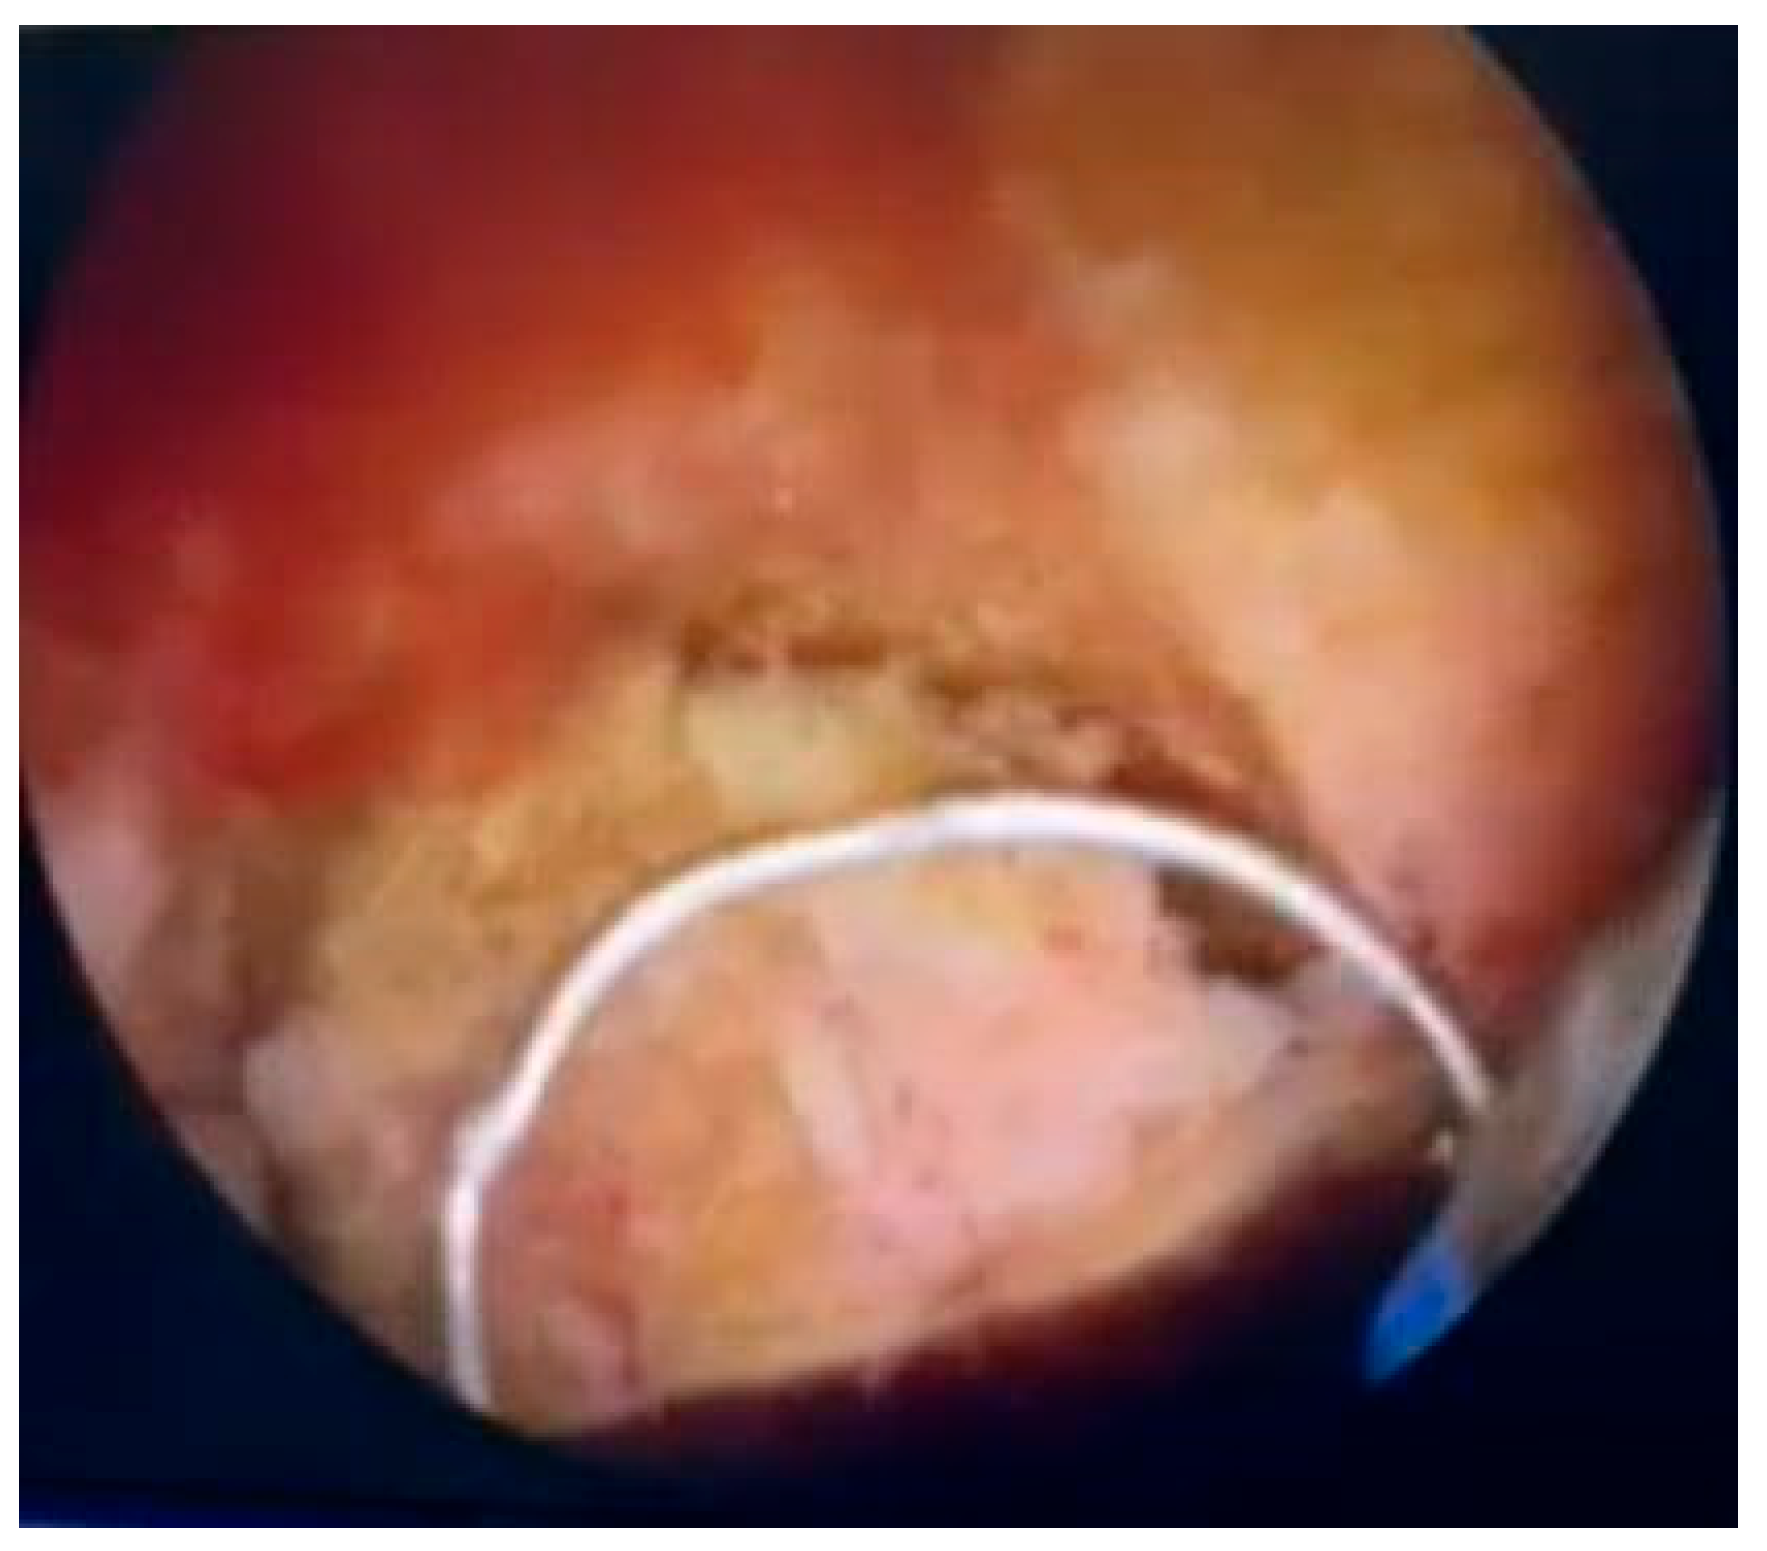

Due to marked bladder wall thickening and the presence of hematuria, the patient underwent transurethral resection (TUR) of a 4-cm papillary lesion located at the bladder dome on 3 October 2025. Intraoperatively, the lesion appeared highly vascularized with a yellowish hue (

Figure 2). The resection was complete, and hemostasis was adequately achieved. The excised tissue was submitted for histopathological and immunohistochemical analysis.